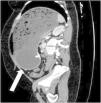

A 45-year-old woman came to the emergency service due to 3 days of ongoing vomiting and significant generalized and progressive abdominal distension. Her past medical history was unremarkable, except for the placing of an intragastric balloon 3 weeks prior. Plain abdominal x-ray revealed an occupied abdomen and bowel loop displacement toward the periphery. A computed axial tomography scan identified severe dilation of the gastric corpus, along with the intragastric balloon (white arrow), which was embedded in the antral region, causing the gastric outlet obstruction (Figure 1 in the axial plane, Figure 2 in the sagittal plane, and Figure 3 in the coronal plane). According to the medical literature, frequency of overall complications from intragastric balloon placement reaches 2.6% and obstruction is one of the most common causes in the early postoperative period, with a frequency of 0.8%. First, a nasogastric tube was placed in our patient to relieve the distension, after which the obstruction was resolved through endoscopic removal of the balloon. After the intervention, the suggested cause was the progression of the balloon and its lodging in the antrum of the stomach, with no excessive filling of that gastric region.